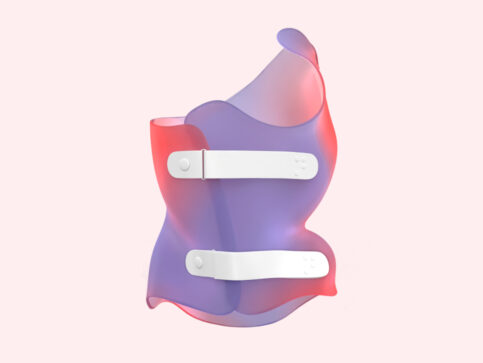

تهدف التقنية الجديدة إلى تحسين دقة تصميم الحزام الطبي بحيث يوزع القوى التصحيحية بدقة على مناطق الانحناء الفعلية. ولتحقيق ذلك، يتم اتباع عدة خطوات متتابعة:

المسح ثلاثي الأبعاد لجسم المريض: حيث يتم عمل مسح كامل للجذع لتحديد مناطق الانحراف بدقة عالية، وهذا يسمح بتخطيط أكثر دقة من الطرق التقليدية.

إنشاء نموذج افتراضي متناظر: يُستخدم هذا النموذج لعكس صورة الجذع بحيث تمثل النسخة المثالية للجسم، مما يسهل مقارنة الشكل المثالي بالجسم الفعلي.

مقارنة الصورة الأصلية بالنموذج الافتراضي: تُستخدم الخرائط اللونية لتوضيح المناطق التي يتجاوز فيها الانحراف 6 ملم، وبالتالي تحديد نقاط الضغط داخل الحزام بدقة.

تخصيص الحزام حسب حاجة كل مريض: يتم تصميم وسائد الضغط بناءً على التحليل الثلاثي الأبعاد، لضمان توجيه القوى التصحيحية نحو مناطق الانحناء الحقيقية، بدلاً من الاعتماد على التقدير البصري فقط.

وبالتالي، يتم الجمع بين الدقة العلمية وراحة المراهق أثناء ارتداء الحزام، مما يحسن النتائج النهائية للعلاج.